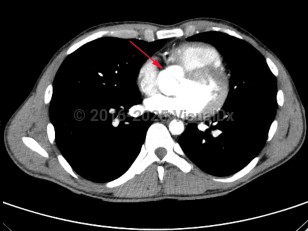

Congenitally abnormal aortic valve with only two functional valve cusps, usually due to fusion of two of the cusps. This is associated with valvular stenosis and/or insufficiency, as well as abnormalities of the aorta including aneurysms and coarctation. It may occur alone or with other cardiovascular abnormalities such as ventricular septal defect, patent ductus arteriosus, and sinus of Valsalva aneurysm.

Common signs and symptoms include chest pain, decreased exercise tolerance, dyspnea, heart murmur, palpitations, syncope, and aortic regurgitation, or patients may remain asymptomatic for a long time. Infective endocarditis, aortic dilation, and aortic dissection are serious complications. A life-threatening association with symptomatic aortic stenosis puts the patient at risk of sudden death.

Common signs and symptoms include chest pain, decreased exercise tolerance, dyspnea, heart murmur, palpitations, syncope, and aortic regurgitation, or patients may remain asymptomatic for a long time. Infective endocarditis, aortic dilation, and aortic dissection are serious complications. A life-threatening association with symptomatic aortic stenosis puts the patient at risk of sudden death.